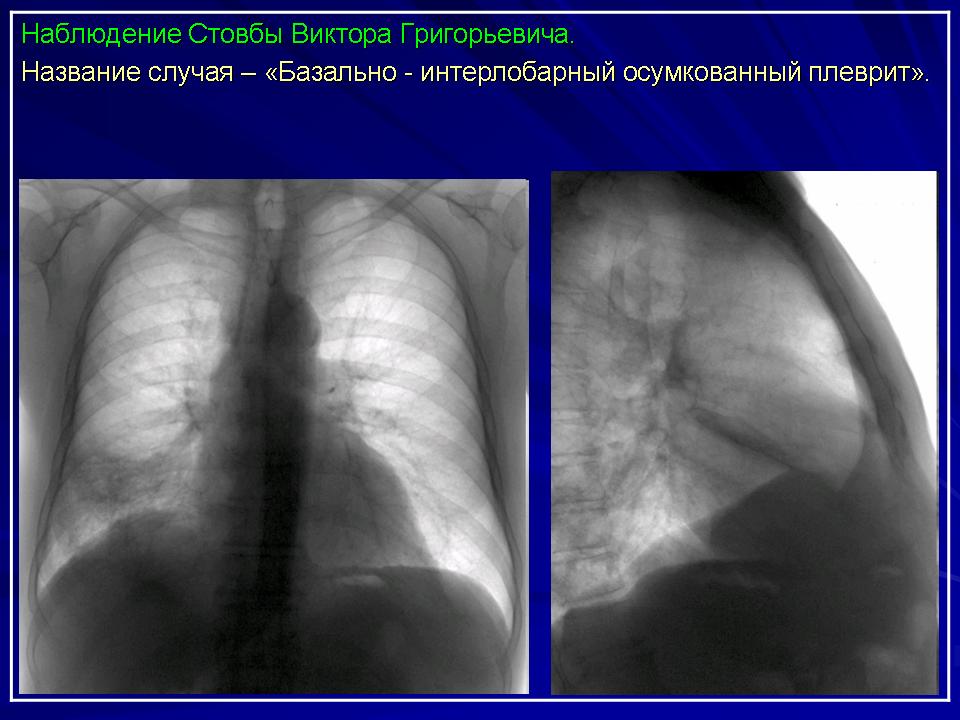

3. Осумкованные интерлобарные плевриты.

Рентгенологическая картина в полной степени зависит от количества экссудата, от локализации, состояния окружающих тканей.

Междолевые осумкованные плевриты являются следствием свободного выпота, как результат «затекания» экссудата в междолевые щели, где и происходит процесс осумкования. Довольно часто процесс осумкования происходит на уровне сердечно-диафрагмальных синусов.

Как правило, исследование только в прямой проекции, не позволяет поставить диагноз. Типичная скиалогическая картина междолевого осумкованного плеврита имеет отображение на боковой рентгенограмме.

Рентгеносемиотика базальных осумкованных плевритов.

Диафрагмальный (базальный) осумкованный плеврит.